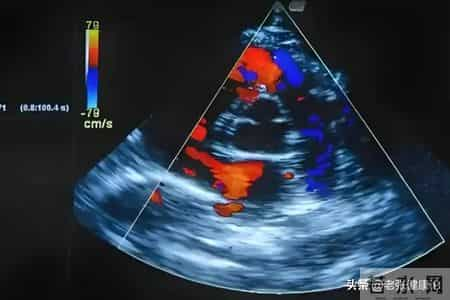

规律随访不可忽视:即便无不适,每年至少进行一次心脏彩超、心电图及血常规监测。发现血脂、炎症标志物(如高敏C反应蛋白)异常,及时调整方案。